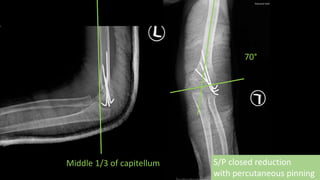

S/P closed reduction

with percutaneous pinning

70°

Middle 1/3 of capitellum

S/P closed reduction withpercutaneous pinning 70° Middle 1/3 of capitellum